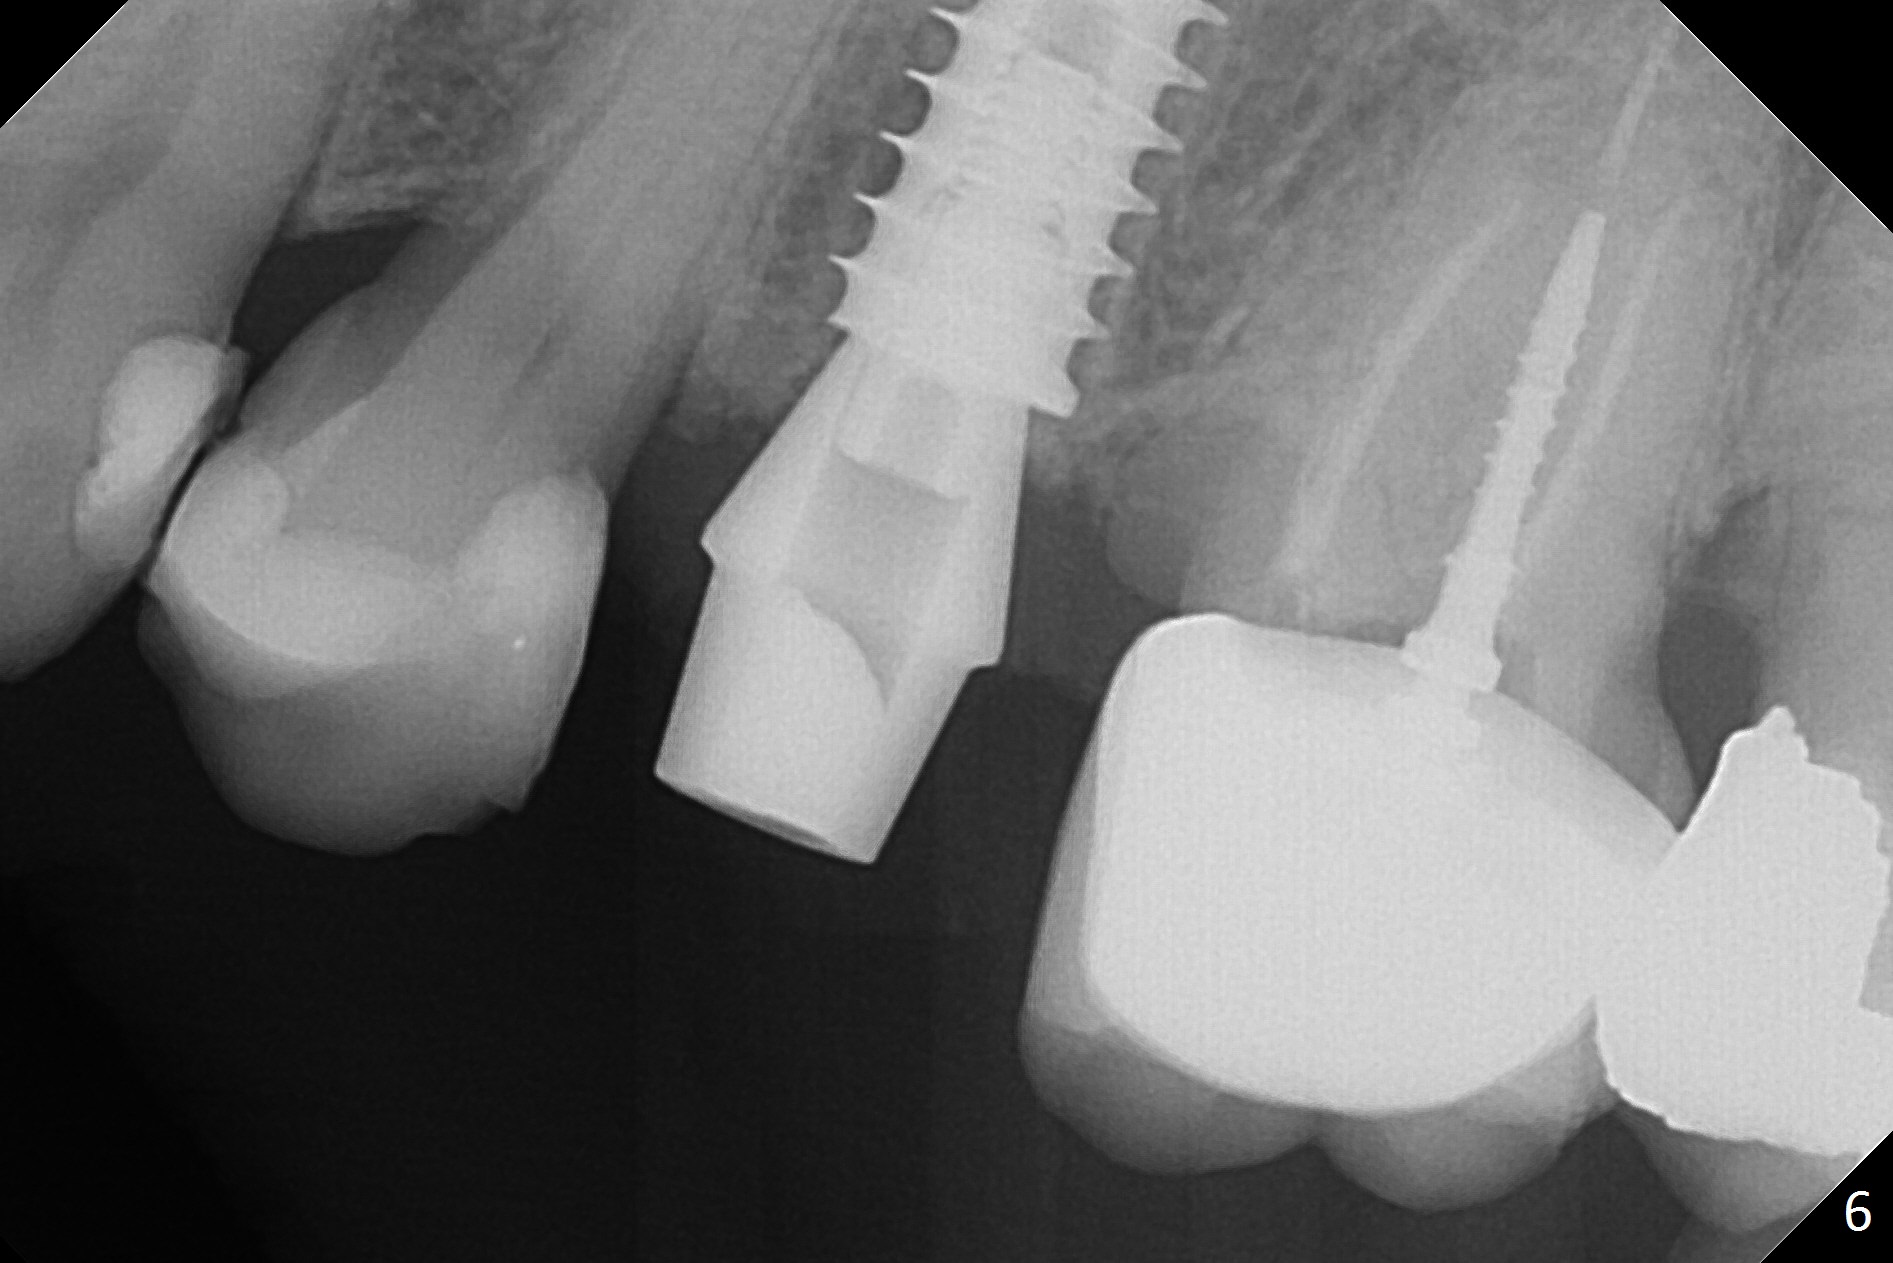

Since the apical native bone is limited at #13 after extraction, no PA is taken until a 4x11 mm dummy implant is placed after 1.6 mm and 3.3 mm drills for 13 mm (Fig.1). After using Lindamann bur to move the osteotomy distal and reusing 3.3 mm drill, the trajectory of a 4.5x11 mm IBS dummy implant improves (Fig.2,3 with low stability). When the implant is removed, the buccal portion of the socket is found to be perforated (Fig.4 P). Although the reason for the perforation is unknown, it is repaired by insertion of a piece of PRF plug, followed by allograft. #1 and 2 in Fig.4 represent the 1st and 2nd osteotomies, as shown in Fig.1 and 2, respectively. The trajectory of the final 5x13 mm implant is acceptable (Fig.5-7, different angulations), so is insertion torque (45 Ncm). After placing a 5.5x4(4) mm abutment, an immediate provisional is fabricated (Fig.8 P) with occlusal clearance (*). The interdental papillae remain in place 12 days postop (Fig.9 *). There is no sign of postop sinus infection. The provisional is loose 18 days postop; the abutment is changed to 5x4(3) mm (Fig.10). It is difficult to catch the mesial margin of the abutment for impression 4 months postop, due to poor oral hygiene and the short cuff (3 mm, Fig.11). The appointment for impression is rescheduled with emphasis on oral hygiene and no wearing the provisional for a few days prior to next appointment. Bone has grown into the space between the 1st and 2nd threads 5 months post cementation (Fig.12) and the bone is normal, solid and dense 2 years 11 months post cementation (Fig.13 >). There is mesial open margin of the tooth #14 (Fig.13,14 *).